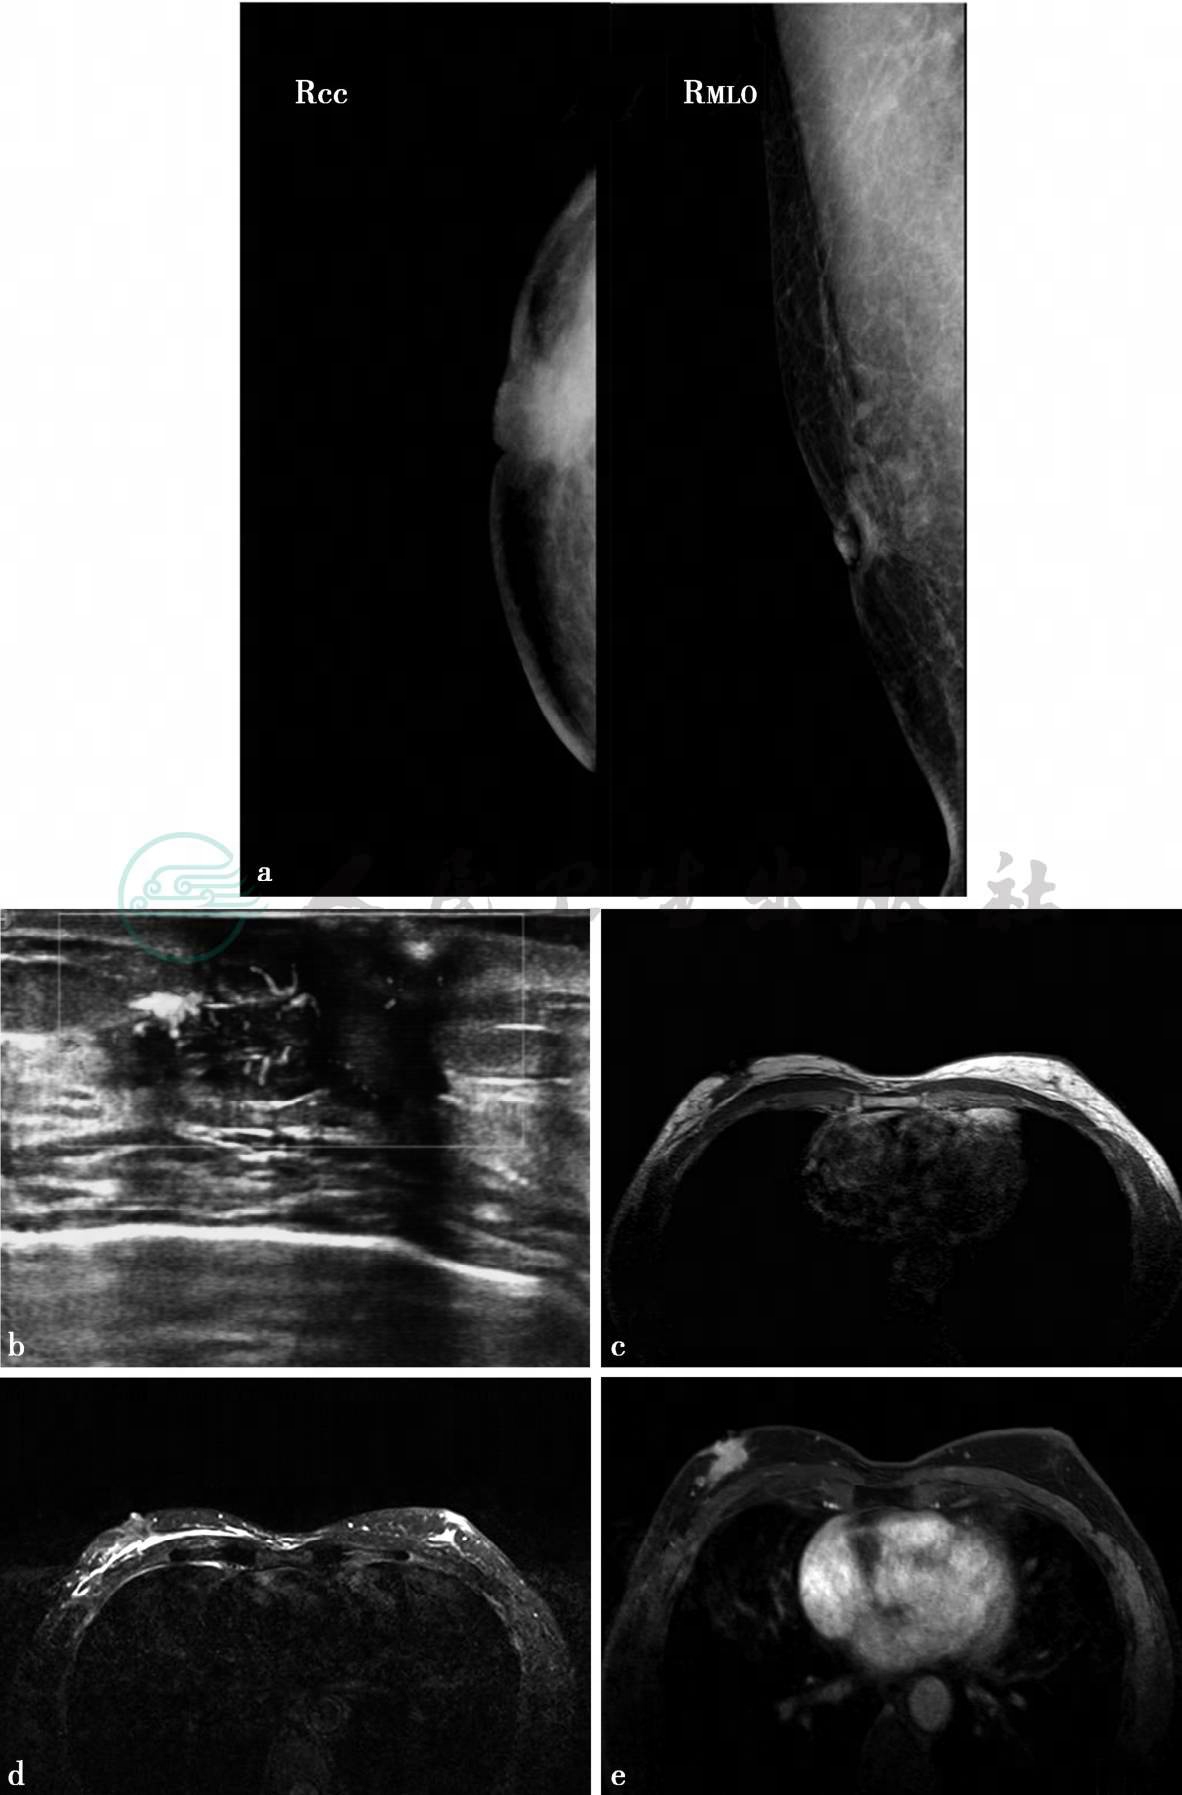

图1 图a,乳腺X线头尾位(CC位)、内外斜位(MLO位)。乳腺X线示乳晕后不规则肿块,边界不清,密度增高,牵拉乳头,皮肤增厚粘连,图b,超声纵切面图。超声示不均匀低回声肿块,边界不清,呈蟹足状向周围延伸,其内及周围丰富血流。图c~f,MRI检查。图c,横断面T1加权成像,图d,横断面T2加权成像,图e,同一层增强抑脂T1加权成像横断面,图f,时间—信号强度曲线。MRI示右乳中央区不规则肿物,边界不清,T1WI、T2WI不均匀稍低信号,动态增强后呈不均匀强化,时间—信号强度曲线呈流出型,乳头内陷并强化